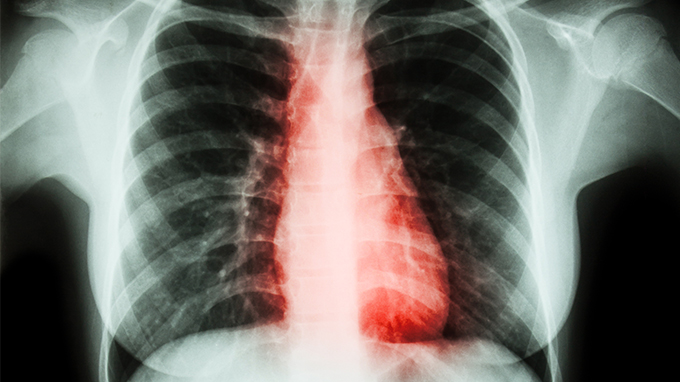

肺癌会引起颈椎痛吗

现如今说起颈椎痛,可能我们都已经觉得习以为常了,工作原因,长时间坐在电脑面前不运动,这个是似乎已经成为常态了。时不时肩膀麻痛,脖子硬的转不了弯,我们都自然而然的归结为颈椎病。我们要特别注意,并不是所有的颈椎痛都是颈椎病,也有可能是肺癌。

为什么肺癌会有颈椎痛的感觉呢?一种情况是,肿瘤长在上边,牵拉胸模可能引起肩膀痛;另外一种情况就是癌细胞转移到锁骨、腰椎、颈部,会压迫神经,这种情况也会引起手麻、肩膀、腰背痛。因为这种疼痛并不典型,所以,很难一下子就推出罪魁祸首就是肺癌。